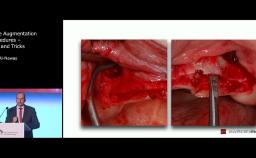

Extraction and immediate implant placement is nowadays considered a reliable treatment option. This approach has certain benefits in preserving the soft tissue architecture and in providing immediate satisfaction of patients. However, key aspects must be taken into consideration in order to insure successful and esthetic outcomes. This lecture aims to highlight the benefits and the limits of extraction and immediate implant placement both in the esthetic zone and in the posterior region. Biological principles, decision-making and surgical techniques will be discussed through clinical research data and illustrated by case presentations.

- understand the surgical key aspect of immediate implant procedures